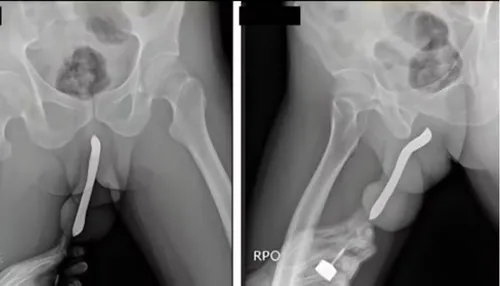

Um relatório baseado no banco de dados da Comissão de Segurança de Produtos de Consumo dos EUA (CPSC) revelou a lista de objetos inusitados retirados de órgãos genitais masculinos e femininos em prontos-socorros americanos. A análise, compilada pelo site Defector com dados referentes a 2024, aponta que itens como baterias, peças de jogos e até utensílios domésticos estão entre os corpos estranhos removidos por equipes médicas.

Embora motivada muitas vezes por curiosidade ou fetiche, a introdução de objetos inadequados no corpo é considerada uma prática de alto risco. Profissionais de saúde alertam que o hábito pode resultar em traumas físicos, infecções graves, perfurações e necessidade de intervenção cirúrgica de emergência.